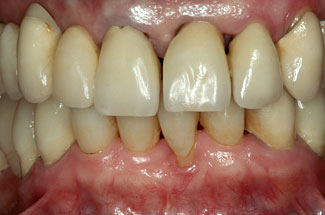

Abbildungen 3-5: Die klinischen Fotographien zeigen den Zustand nach der ersten professionellen Zahnreinigung.